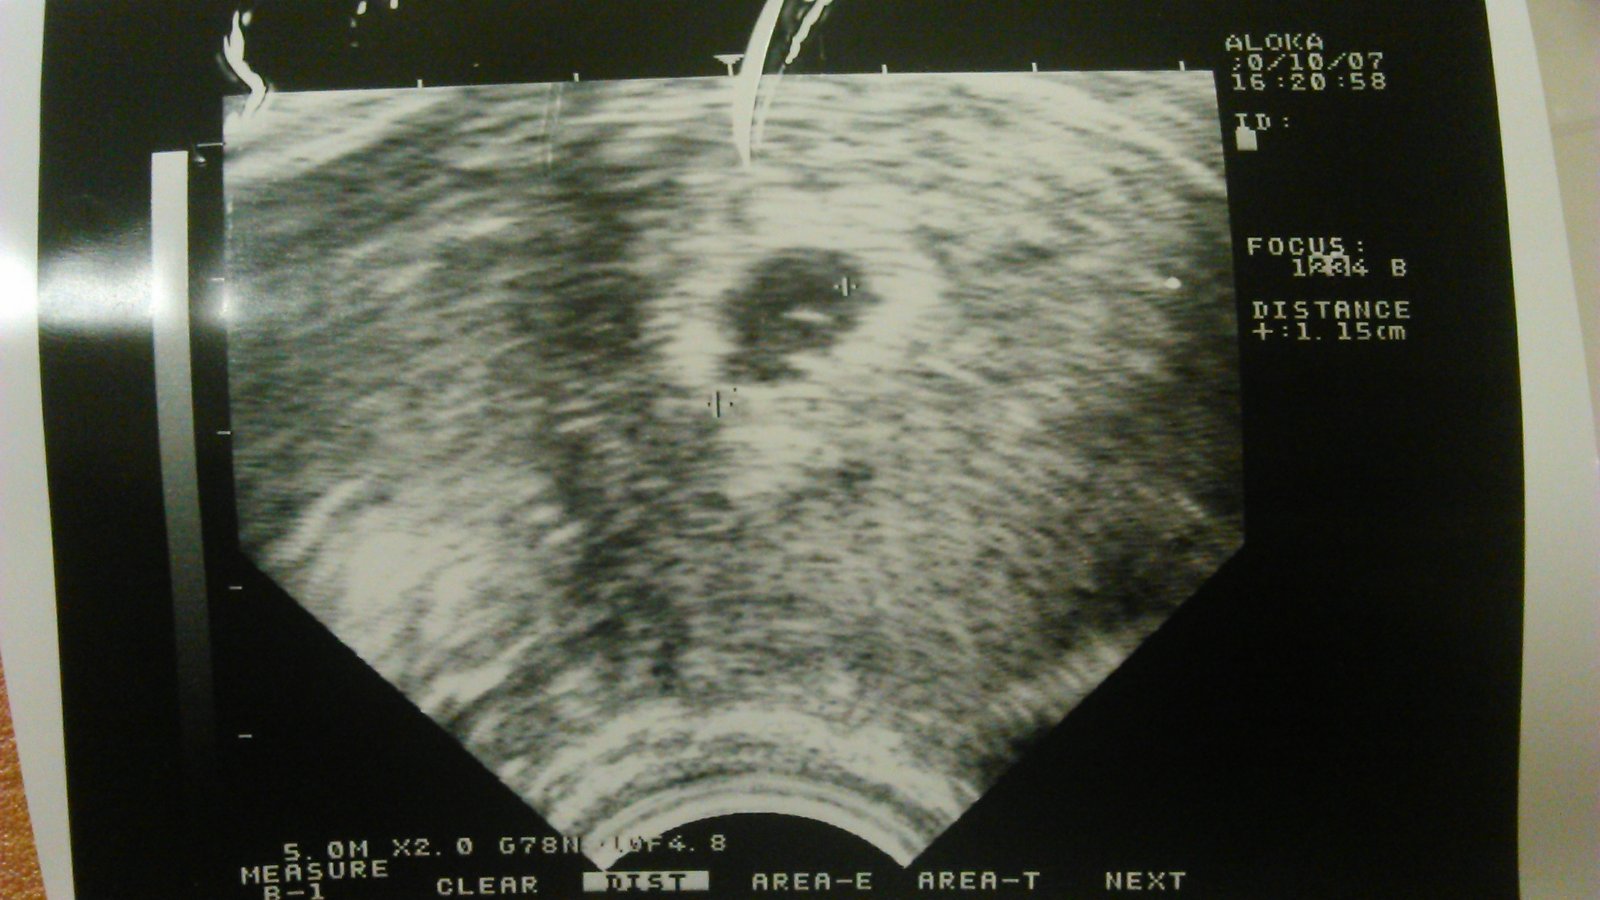

To je nasa chrumka 1 cm mame 😉